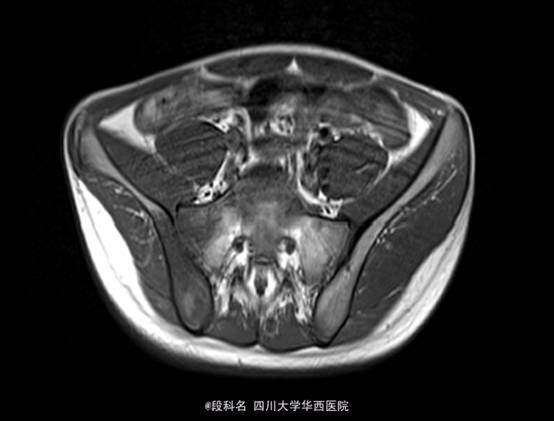

查体:右髋局部无红肿,有压痛,皮温不高,感觉无减退。右侧髋伸屈、外展、内收,因疼痛无法评测。右膝屈曲4级,伸膝3级,踝背伸、跖屈4级 。左侧肌力正常,肌张力正常。右侧直腿抬高试验40°(+),加强实验(+),右侧4字实验(+)。辅助检查:当地医院CT检查示:L4/5椎间盘轻度膨出,L5/S1椎间盘轻度突出,建议MRI检查。我院血常规示:血小板计数 425 10X9/L,白细胞计数 12.26 10^9/L,中性分叶核粒细胞绝对值 8.34 10^9/L。生化示:血沉53.mm/h,C反应蛋白(CRP)42.80mg/L。痰涂片抗酸染色(连续3次):未查见抗酸杆菌。免疫球蛋白A 4050.00 mg/L ↑ 免疫球蛋白M 2240.00 mg/L ↑C-反应蛋白 31.80 mg/L ↑。T细胞亚群正常。CD3细胞亚群 71.40 %CD4细胞亚群 37.00 % CD8细胞亚群 29.80 % CD4/CD8比值 1.24。痰培养示:产酸克雷伯氏菌 混丛,较多。结核抗体检测 阴性 。骨盆MRI示:右侧骶髂关节面骨质见斑片状长T2WI及长T1WI信号,关节间隙模糊、局部狭窄,邻近髂腰肌、梨状肌、臀肌群见斑片状T2WI高信号影。左侧骶髂关节及双侧髋关节未见确切异常。